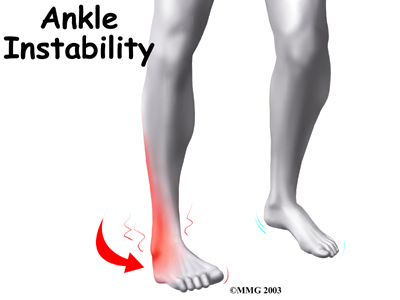

Mild syndesmosis sprains usually involve a stretch or slight tear in only one of the ligaments making up the syndesmosis. Moderate tears of the ankle syndesmosis may lead to ankle joint instability, which make the ankle mortise loose. In severe tears of the ligaments, the ends of the tibia and fibula actually spread apart. This condition is called diastasis.

If the problem has been ongoing, patients may have pain due to an unstable ankle joint. They may feel vague pain around the ankle. Attempts to turn or twist the injured foot may cause sharp pain in the ankle joint. Pain may radiate upward along the side of the lower leg. And the ankle may feel weak, like it can't be trusted to hold steady, even during routine activities.

Unstable Ankle Joint